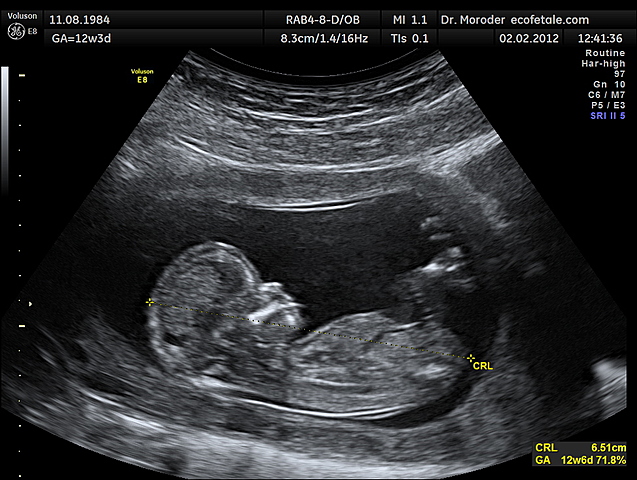

Le développement du cerveau aux périodes prénatales dépend, comment la mère se nourrit et prend soin de leur corps pendant ce temps. Si elle fume, consomme les drogues ou l’alcool ça va affecter le bébé énormément quand ils sont nés, sois physique ou mentale. Sois des problèmes de santé mentale, leur système nerveux, être prématuré ou le risque d'avoir des malformations congénitales, etc. C'est important pour la mère de prendre certaines vitamines pour que le bébé reste en santé.

• Période prénatale (photo)